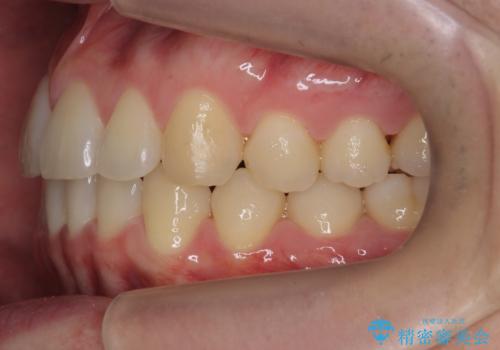

- 右上の前歯が内側に入っているのを気にして来院。

右上の奥歯を後ろに移動して、前に出すスペースを確保してから並べました。

奥歯を後ろに送るために、矯正用インプラントを使用しています。

前歯が内側に入っていると、笑った時にそこが黒くなり、歯が抜けたように見えます。

口を開けたとき、笑顔の印象が大きく変わり、大変喜んでいただけました。